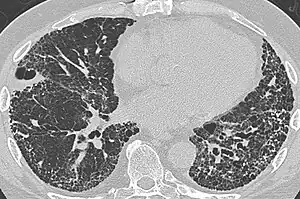

| CT scan of a patient with UIP. There is interstitial thickening, architectural distortion, honeycombing and bronchiectasis. | |

UIP may be diagnosed by a radiologist using computed tomography (CT) scan of the chest, or by a pathologist using tissue obtained by a lung biopsy.

Radiologically, the main feature required for a confident diagnosis of UIP is honeycomb change in the periphery and the lower portions (bases) of the lungs.[3]

On high-resolution computed tomography (HRCT), the following categories, depending on imaging findings, have been recommended by a collaborative effort by the American Thoracic Society, European Respiratory Society, Japanese Respiratory Society, and the Latin American Thoracic Society:[4]